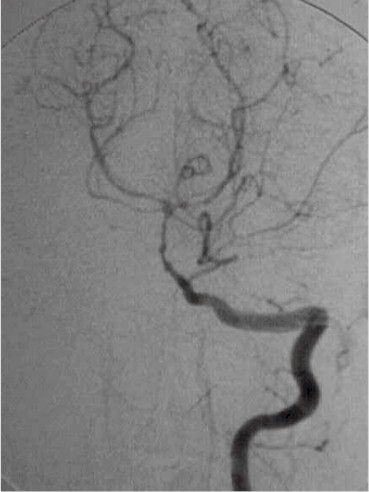

Angioma

encefalico. |